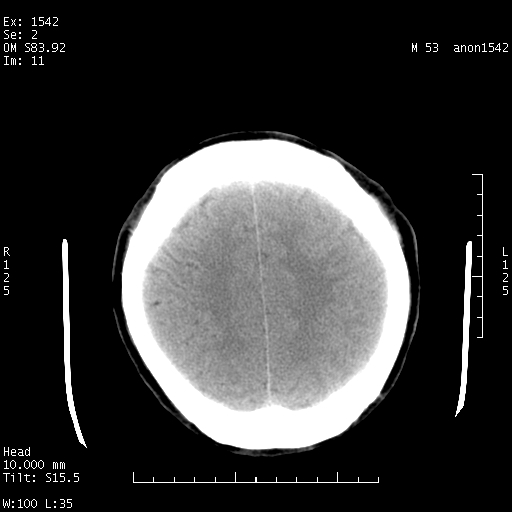

标题: CT10811:M53Y,头痛一月.其它没有什么 [打印本页]

标题: CT10811:M53Y,头痛一月.其它没有什么

左侧鞍旁不规则低密度,此区域和侧脑室有液平。若无外伤史。考虑左侧鞍旁表皮样囊肿自发破溃。

鞍旁颞叶低密度灶.其中散在空气影.还有侧脑室.是否考虑脑脓肿(请提供病史情况)

1 囊性肿物. 2 请楼主上传介少病人资料. 3 表皮样囊肿或胆脂瘤都在考虑范围内,确切的不知ct值是多少.4了解病史后在缺定.

1 是否有外伤或原发出血微创术后改变. 2 期待病史.